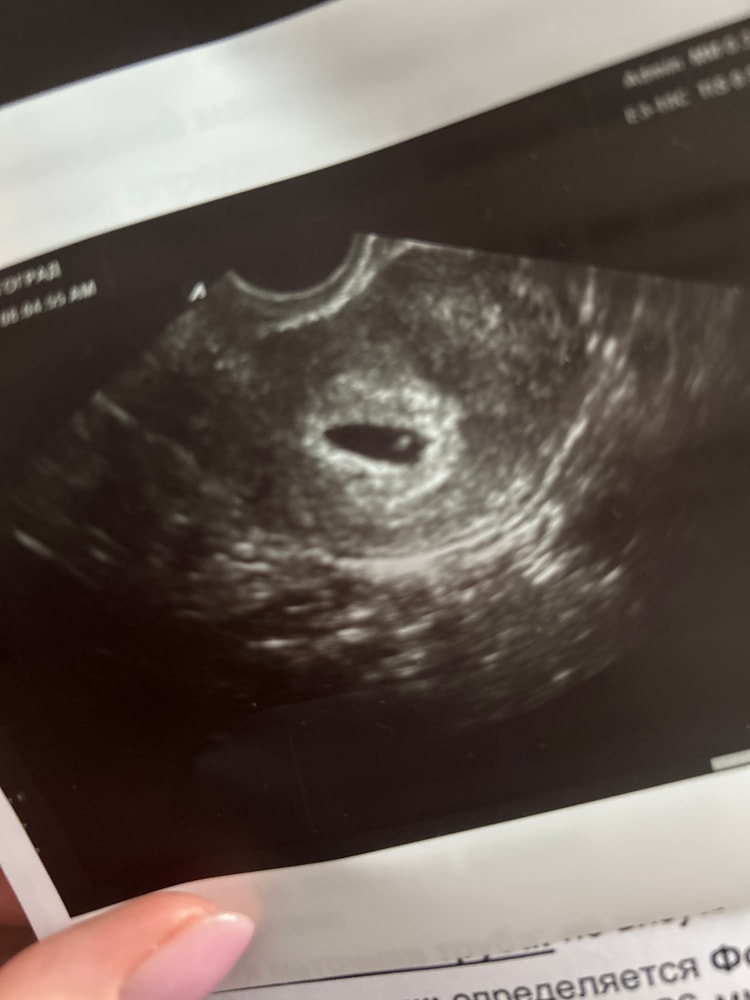

21дпп узи ❤️

Результаты УЗИ

СВД 6,7-10мм

КТР 3,2мм

сердцебиение +